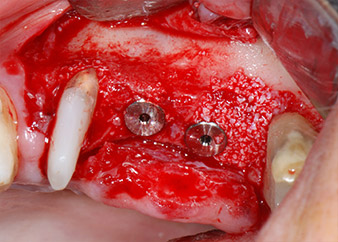

Im folgenden Schritt wurde das jeweilige Implantatbett an den Positionen 25 und 26 mit rotierenden Instrumenten in einem Winkelstück mit einem Übersetzungsverhältnis von 20:1 (WS-75 L G, W&H) und einem vor Kurzem aktualisierten leistungsstarken Implantatmotor präpariert (Implantmed, W&H) (Abb. 8 und 19).

Die Abschlusspräparation am Sinus erfolgte wieder mit einem piezochirurgischen Instrument.

Vor der Insertion der Implantate und nach Überprüfung der intakten Schneiderschen Membran (Abb.9) wurde der interne Sinusboden an beiden Implantatpositionen mittels eines xenogenen Knochenersatzmaterials (Abb. 10) augmentiert.

Dann wurden die Implantate (Restore, Keystone Dental) mit dem Implantatmotor eingesetzt (Abb. 11 und 12).